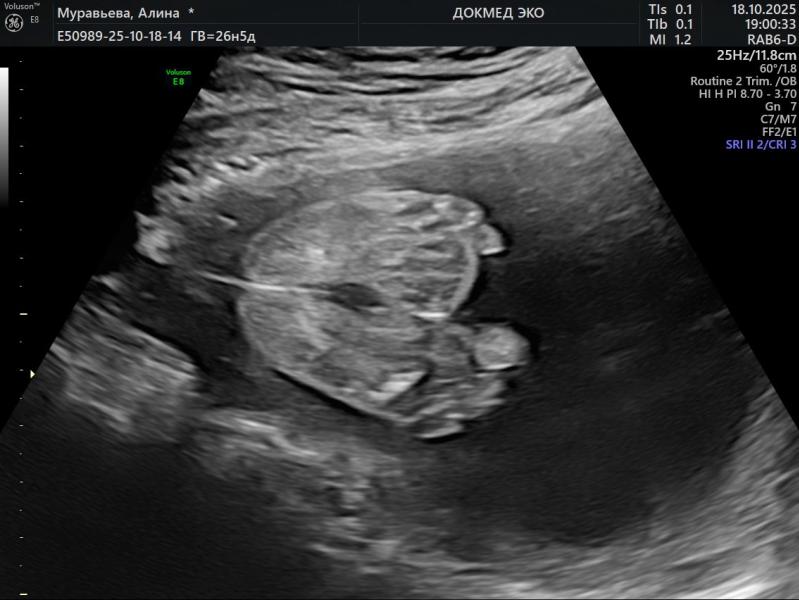

Вчера были на узи, в 26.6 недель 1062 грамма весим:)

Сделали 3-4д узи, какой он хорошенький… еще писюн показывал😂

Сложился как книжечка, ножки к лицу

Нос мой!😄 надо же…